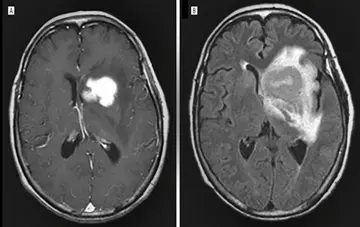

شماره ۱۱۵۴

لنفوم اولیه سیستم عصبی مرکزی